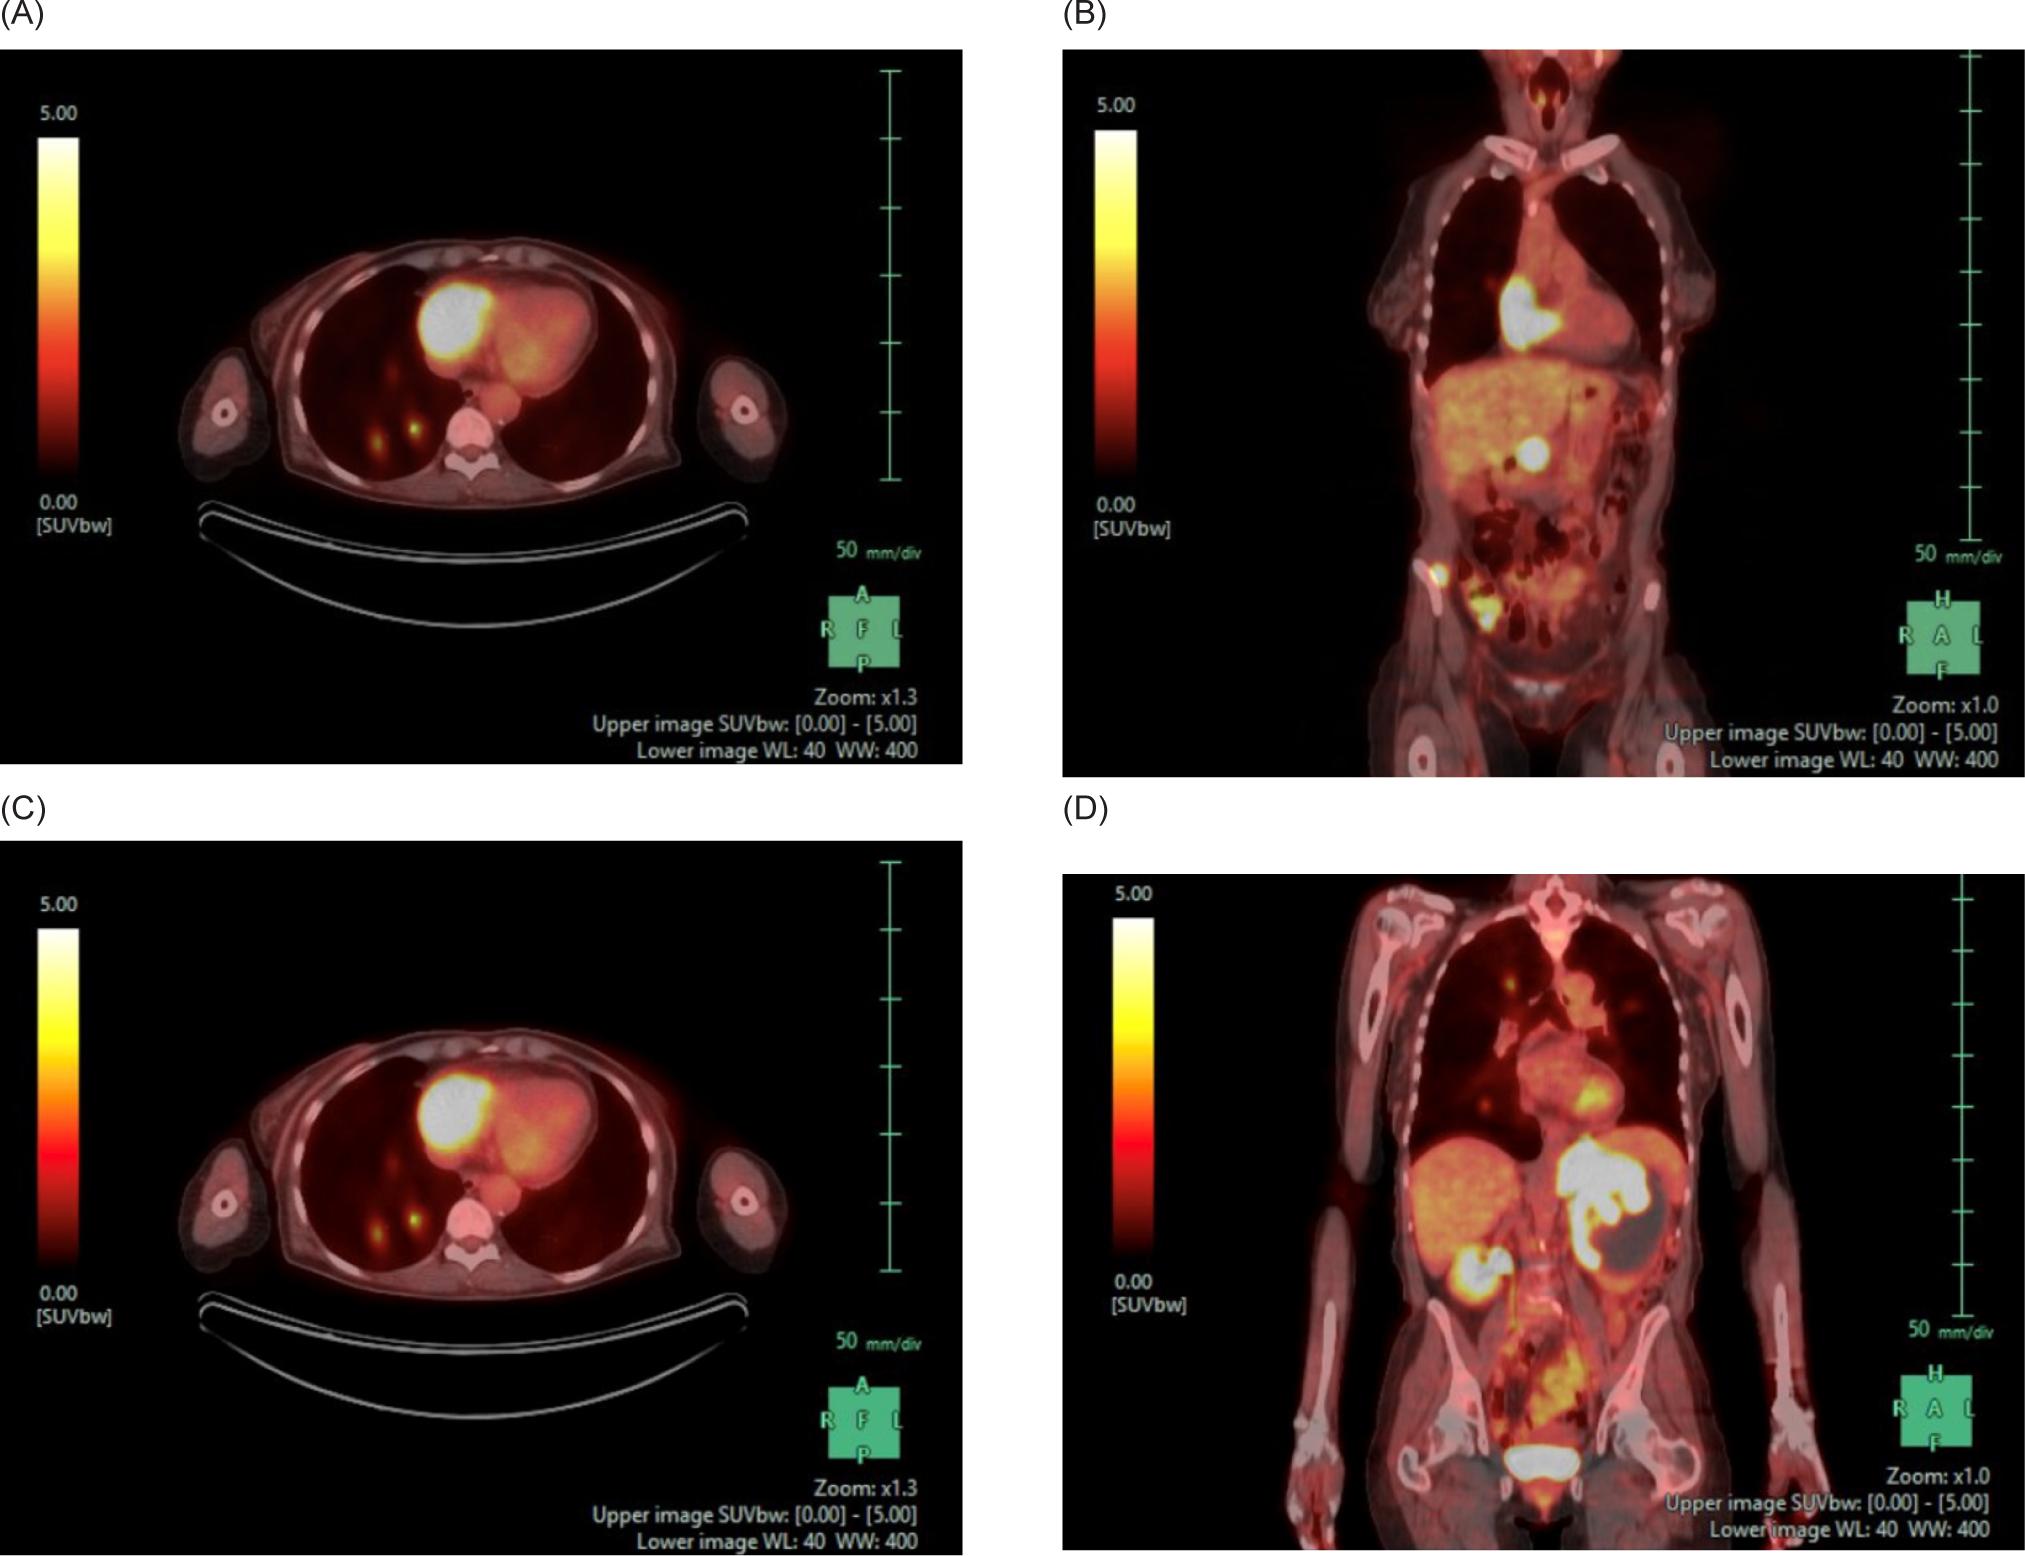

A 59-year-old female smoker with history of hypertension and hyperlipidemia who was screened for lung cancer with yearly low-dose CT scans was incidentally found to have a large left renal mass. Further evaluation via CT revealed a complex enhancing renal mass measuring 9.2.2 × 9.3 × 12.4 cm with extension into the left psoas muscle and abutting the pancreatic tail, spleen, and stomach (Figure 1). The patient underwent excision of a soft tissue mass, and surgical pathology was consistent with sarcoma. PET-CT scan revealed multiple avid lesions including lung nodules of up to 1.5 cm, a left adrenal mass, retroperitoneal adenopathy, and soft tissue metastases in the pelvic muscles as well as a lesion near the right atrium (Figure 2). An echocardiogram was performed in order to further evaluate the cardiac finding on the PET-CT scan, which revealed a 3.5 × 3.4 cm mass attached to the right atrial free wall, which was thought to represent a large thrombus or cardiac tumor, as well as a 0.75 cm mass noted on the atrial aspect of the IVC-RA junction likely representing the thrombus. Left ventricle ejection fraction was normal at 65%. The patient was instructed by her cardiologist to present to the Emergency Department for further evaluation given these findings. On presentation, the patient reported intermittent left flank pain, EKG was normal sinus rhythm with no acute ST changes, and CTA scan revealed likely invasion of perivascular nodules in the right upper lobe into subsegmental pulmonary arterial branches with associated pulmonary emboli within the distal subsegmental and more distal branches. The following day, cardiac MRI confirmed an intra-cardiac tumor occupying the entire right atrium with extension through the myocardium into the epicardial space and through the tricuspid valve into the right ventricle (Figure 3). MRI brain revealed three lesions consistent with metastatic disease. Renal biopsy was consistent with clear cell RCC with sarcomatoid features (Figure 4). Immunohistochemical studies were positive for desmin, PAX8, and myogenin, and negative for CK7. Patient was identified as poor risk per International Metastatic RCC Database Consortium (IMDC), with a median survival of 7.8 months. The patient received Ipilimumab and Nivolumab for one cycle, followed by Nivolumab only due to complication of diarrhea requiring steroid therapy. After three months of therapy that included three cycles of total therapy, she was noted to have partial response per Response Evaluation Criteria in Solid Tumors (RECIST) criteria. The patient will be continued on Nivolumab. The patient was also treated with gamma knife radiosurgery for her brain metastases.

Figure 3: Cardiac MRI. (A) Transverse and (B) coronal views demonstrating a large intra-cardiac tumor occupying the majority of the right atrium extending through the myocardium into the epicardial space and through the tricuspid valve into the right ventricle.